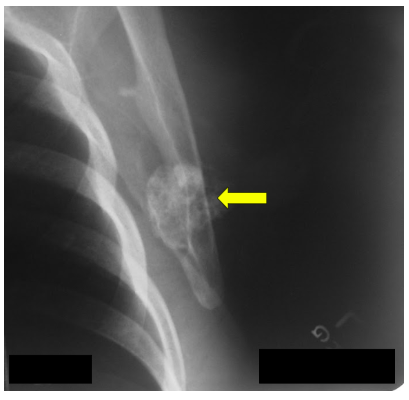

Radiographic imaging is used to help form a diagnosis of secondary chondrosarcoma. These include X-Ray, MRI, CT and Bone Scans

An example of an X-Ray is shown.